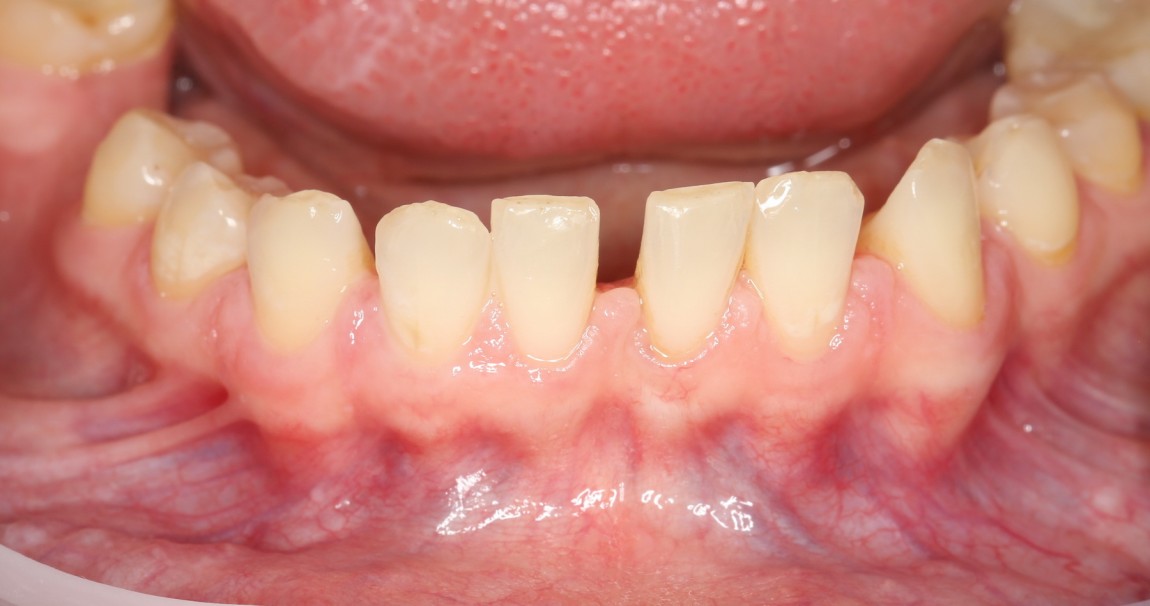

Фотография, примерно через месяц после операции:

Сравните с тем, что было:

Со временем, рубцы размягчатся и станут почти незаметными. Теперь пациентка может спокойно приступать к исправлению прикуса, которое, в свою очередь, является частью еще более грандиозного плана стоматологического лечения: предстоит еще и имплантация, и протезирование, и много чего еще.